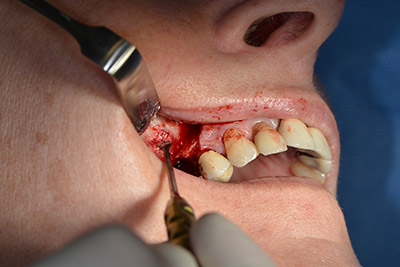

The 59-year-old patient presented with an advanced case of periodontitis, describing an unpleasant feeling and poor taste from the first quadrant in a distal direction. The clinical examination revealed generally enlarged periodontal pockets and very advanced bone atrophy in regions 16 and 14. The radiology confirmed the findings (Fig. 1). Teeth 16 and 14 could not be retained.

Image 1: Orthopantomogram with bone atrophy in region 16–14. *